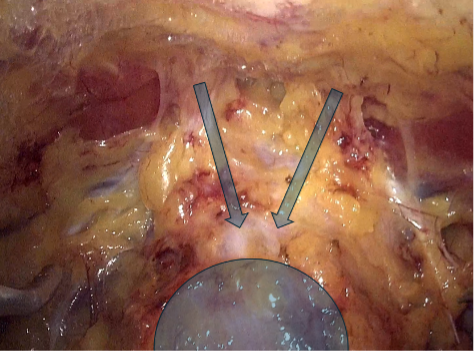

Los tumores testiculares no seminomatosos en etapa I tienen un riesgo de presentar micro metástasis en el retroperitoneo cercano al 30% de los casos, especialmente, si hay factores de riesgo en la biopsia del tumor testicular. Es hasta ahora controvertida la opción terapéutica a ejecutar y la linfadenectomía lumboaórtica (LALA) es una de ellas. También tema actual de controversia es la conveniencia de realizar la uni o bilateralidad de la linfadenectomía. La gran ventaja de la LALA es que tiene cerca de un 100% de sensibilidad y especificidad, aún en la era de la tomografía por emisión de positrones (PET) y representa una alternativa a los protocolos de observación (40-42). Sin ahondar en la controversia, explicaremos en forma sencilla esta técnica cuya mayor complejidad reside en el posible daño a un vaso mayor pudiendo transformar un procedimiento reglado en una emergencia. Otro aspecto a considerar es la edad del paciente en que la preservación de la función eyaculatoria es fundamental. En estos casos la ubicación del paciente es igual que la anteriormente descrita para la cirugía renal. Utilizamos el trócar de la cámara en la cicatriz umbilical y el trócar más caudal desplazado hacia la fosa ilíaca correspondiente. Una vez logrado el pneumoperitoneo, tan importante como la minuciosa extirpación del espécimen linfático, es lograr previamente una amplia exposición de los límites a disecar: si el límite superior es la vena renal, la disección debe abarcar al menos unos centímetros sobre el hilo renal y lo mismo para los demás límites. De esta manera se podrá efectuar un procedimiento cómodo, completo y seguro. Muchas veces se falla en estos detalles básicos que pueden frustrar el éxito de la cirugía y poner en riesgo al paciente. Indistintamente del lado, el abordaje que realizamos es transperitoneal. Hay limitadas experiencias de abordaje retroperitoneal que no han sido suficientemente reproducidas y podrían tener su espacio solo en excepcionales circunstancias(43). En ambos casos es necesario movilizar ampliamente el colon respectivo para exponer los grandes vasos y los límites de disección propuestos por Weissbach (Figura 31). Los límites superiores están determinados por el borde inferior de las venas renales y el límite inferior por el cruce del uréter sobre los vasos ilíacos. Los límites laterales están demarcados por los uréteres. En el lado derecho es necesario levantar el hígado y para esto utilizamos el Endo Retract™ II o también se puede utilizar una pinza de 5 mm desde el apéndice xifoides fijado en la pared costal. Es necesario realizar una maniobra de Kocher para movilizar el duodeno y exponer los grandes vasos al lado derecho. Logrado este tiempo, se extirpa todo el material linfático de las regiones para cava, supra cava e interaorto cava. Rutinariamente extirpamos los ganglios supra aórticos por sobre la arteria mesentérica inferior. Utilizamos una pinza y disector común para separar el espécimen linfático de las estructuras vasculares. Cuando tenemos una perfecta identificación de éstos, usamos un LigasureTM Maryland de 5 mm para sellar y seccionar los linfáticos. Evitamos seccionar los vasos lumbares ya que, dado que, de existir metástasis ganglionares, éstas se desarrollarían ventrales a los vasos(44). Una vez liberado el espécimen linfático, este se extrae en una bolsa de PVC por uno de los sitios de punción. Ocasionalmente después de establecida una rigurosa hemostasia, instalamos en el lecho quirúrgico una matriz hemostática con trombina sintética para disminuir el riesgo de un linfocele. Para el lado izquierdo realizamos el mismo procedimiento descrito anteriormente, evitando disecar y lesionar los nervios simpáticos responsables de la eyaculación anterógrada, ubicados por sobre la aorta debajo del nacimiento de la arteria mesentérica inferior (45) (Figura 32).